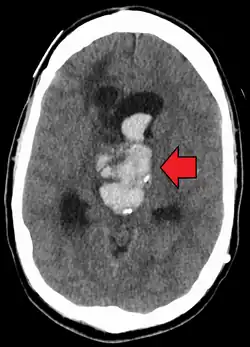

| Axiali CT scan of a spontaneous intracranial hemorrhage | |

A non-contrast CT scan (computed tomography) of the brain is commonly used as the initial imaging modality in suspected cases of intracranial hemorrhage. CT is preferred in emergency settings due to its speed, availability, and high sensitivity for detecting acute brain injuries, enabling rapid triage and surgical decision-making. Examples of brain diseases that require urgent intervention are: large-volume hemorrhage, brain herniation, and cerebral infarction. Additional advantages of CT imaging include its effectiveness in detecting bony fractures, vascular injuries, and cerebrospinal fluid (CSF) leaks.